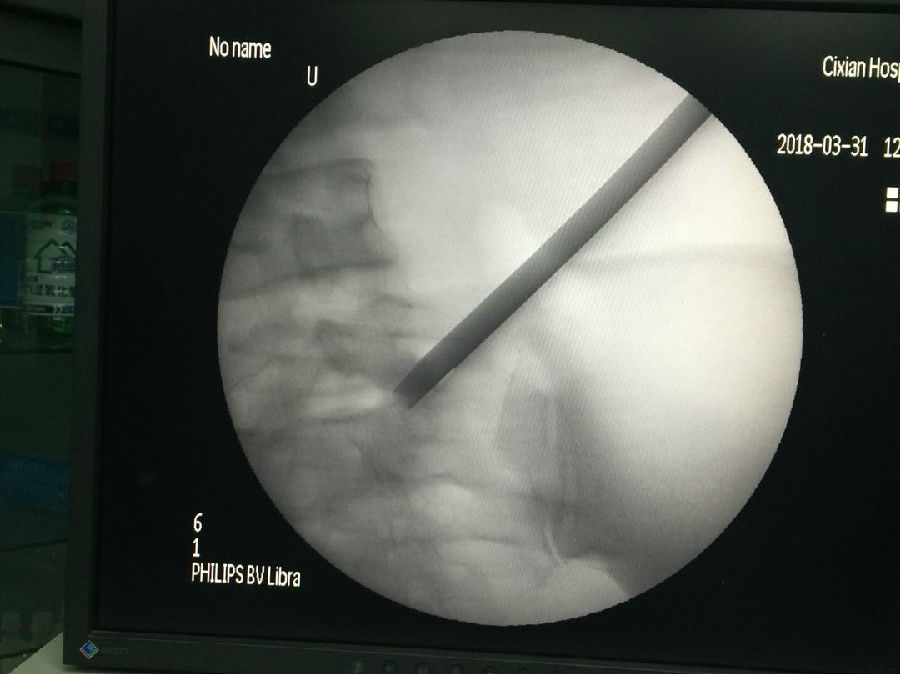

近日收一腰痛患者伴左下肢放射痛十余年,曾到多地求医,效果均不理想。来我院就诊后,通过腰椎动力位X线片及MRI等检查诊断为腰椎间盘突出合并腰椎管狭窄症(L5-S1),考虑到患者病史体征,经科室主任及专家讨论后,决定实施微创手术。与按摩和传统手术的治疗方法不同,微创手术是在局麻C型臂透视定位下,利用孔镜小通道技术操作将腰椎间盘及骨性组织摘除,创口仅0.5cm,创伤小、见效快、费用低、无痛苦。术前患者左腿疼痛无法伸直和站立,术后腿疼症状完全消失,第二天即可在家属搀扶下下地活动,手到病除的手术效果赢得了患者及家属的满意和好评。